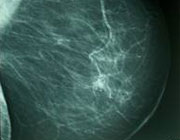

En el Foro de discusión "Tamizaje del cáncer de mama en México: ¿a qué edad es recomendable iniciar?", del CONGISP 2011, se debatió acerca de la edad y la frecuencia con la que deben llevarse a cabo las mastografías de tamizaje en México. |